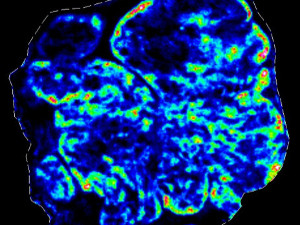

Illuminating tumour micro environments

Advanced technical imaging capabilities and research projects supported by MWC are helping to identify new prognostic and diagnostic biomarkers to advance potential therapeutic tar

New imaging improves our understanding of the immune system

Maurice Wilkins Centre researchers have used novel imaging technology to reveal the structure and inner workings of entire lymph nodes, core components of the body’s immune system.

Mapping microscopic worlds

Maurice Wilkins Centre researchers have used unique microscopic imaging techniques to peer into the three-dimensional structure of blood vessel networks – and new computational tec

New technologies for imaging the human body (2012)

New Zealand technologies being developed to perform delicate new procedures, locate sites where cancer drugs are active, and model a person’s entire skin, were just some of the top